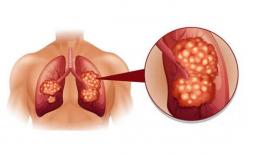

dấu hiệu ung thư phổi

Ung thư phổi là khối u ác tính có nguồn gốc từ niêm mạc phế quản của phổi, tỷ lệ mắc bệnh và tử vong...

Ung thư phổi là khối u ác tính xuất hiện trong mô phổi, là một trong những khối u ác tính phổ biến nhất trên...

Ung thư phổi là khối u ác tính xuất hiện trong phổi, là căn bệnh ác tính có tỷ lệ tử vong cao nhất trong...